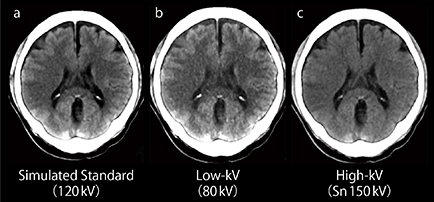

脳梗塞の診断において,頭部CTではearly CT signの評価がきわめて重要である。当院では120kV相当のCT画像,Low-kV画像(80kV),High-kV画像(Sn 150kV)の3点で診断を行うが,当初はearly CT signの評価にはLow-kV画像が最適と考えていた。しかし,実際に画像を比較してみると,Low-kV画像は辺縁のアーチファクトやノイズが多くわかりにくい(図3 b)。一方,High-kV画像は浮腫による吸収値の下がり方が大きく,ノイズが少ないため病変を確認しやすい(図3 c)。また,脳梗塞の早期にて観察されるhyperdense signもHigh-kV画像の方が観察しやすい。Monoenergetic imageおよびSpectral HU Curveによる解析でも同様の結果であった。

図3 急性期脳梗塞における120kV相当の

CT画像Low-kV画像,High-kV画像の比較